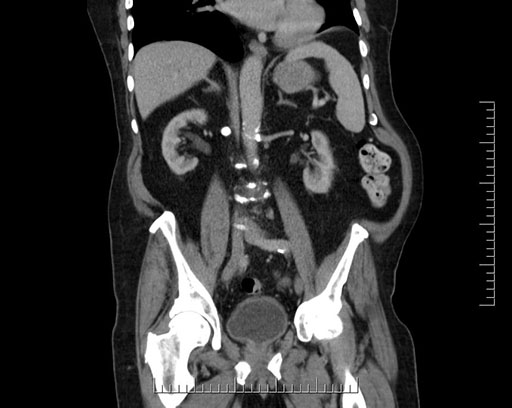

Imaging Analysis

Look through the patient's CT scan to identify any areas of concern for the necessary procedure.

Based on your CT findings, which issue(s) would give reason for "planned slowing down moment(s)" in this case?